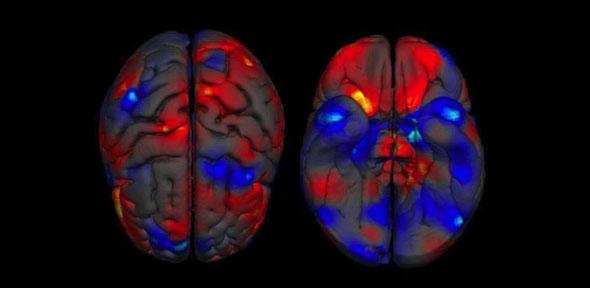

Datu horiek alderatuta, ikertzaileek ikusi dute alde nabarmenak daudela gizonezkoen eta emakumezkoen garunen egitura jakin batzuen bolumenetan. Alde horiek bereziki handiak dira sistema linbikoan eta hizkuntzarekin lotutako eremuetan. Hain zuzen ere, ikerketa askok jarri izan dute agerian sistema linbikoa garatuagoa dagoela gizonezkoetan emakumezkoetan baino, eta alderantzizkoa gertatzen dela hizkuntzarekin lotutako egiturekin. Hortaz, ez da harritzekoa azterketa bateratuak emaitza hori baieztatzea.

Ikertzaileek garrantzia eman diote horri, eta adierazi dute aurrerantzean ezingo dutela diferentziarik ez balego bezala jokatui, “batez ere, gizonezkoetan edo emakumezkoetan ohikoagoak diren gaixotasun psikikoak ikertzean”.